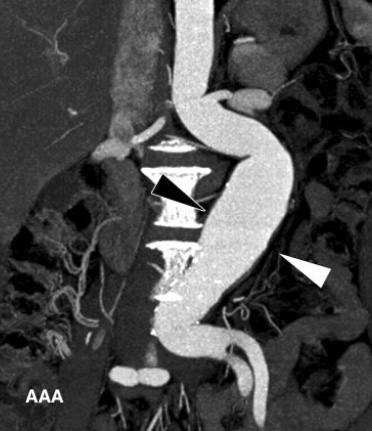

- Anévrismes aortiques

- Dissections aortiques

- Anévrismes Aortiques (Aortes peu calcifiées car patients jeunes)

- Dissections Aortiques (Parfois récurrentes avec des dissections en Triple Canon)